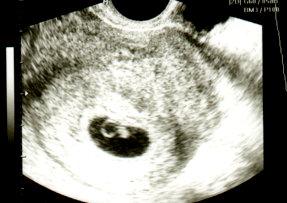

So kann das neue Jahr kommen *wein* habe seid heute halsweh und husten, Ich war am Sa Mittag wegen schmerzen und leichtem bräunlichen Ausfluss im KH dort bin ich auch gleich an die reihe gekommen, Blut Urin das ganze dann ab oben auf die frauenstation dort hat sie US gemacht und konnte zwar eine etwas gewagsene fruchthöle sehen aber kaum was drinnen erkennbar nur ein ganz kleiner strich ob Kind oder dottersack mehr vermuttung als alles andere der strich war übrigens nur 3,7 mm bei 6+3 aber laut US wäre ich dann 6+0 gewesen, so dann fertig schaute sie mich fragend an, und sagte ich rufe den Oberarzt an gehen sie bitte ins Wartezimmer 1 Stunde später sagte sie wir müssen auf das blutergebnis warten was für Blutgruppe sie haben sagte ich die weiß ich a resus negtaiv sie wir müssen trotzdem warten ok wie lange dauert das war unsere frage kommen sie morgen um 11 wieder ok gesagt getan wir am nächsten Tag wieder hin ...... was denkt ihr wann ich dran war ...... Um sage und Scheibe 17 Uhr um gesagt zu bekommen sie hatten recht mit ihrer Blutgruppe, ich bekamm dann noch eine rohpylack spritze mit dem Satz als von dem Kind Blut in ihren Kreislauf gelangen sollte, und dann durften wir heim wenn die schmerzen mehr werden sollten, sollten wir noch mal kommen .... Hammer oder????? Sorry das es so lang wurde versuche noch das Bild vom Kh an zu hängen. Sollte laut Rechner hier heute 6+5 sein.

Ohje das ist ja der Horror Du tust mir richtig leid! Leider bin ich kein Arzt und sehe auf deinem aber auch eine Fruchthöhle mit einem Punkt den ich als Dottersack deuten würde und einen Strich der der dein kleines sein könnte. Ich hänge dir mal zum Vergleich mein Bild an. Da war ich laut meiner Berechnung 7+0. Aber die Berechnungen stimmen ja nur selten

Huhu danke dir für das süsse Foto ja da sieht man deutlich mehr, ich bin ja auch kein Arzt aber für mich sieht das Bild so aus von mir als würde es auf jedenfall richtig in der schleimhaut sein also da wo es auch hin muss Alle Ärzte sagen aber auch das meinegebärmutter nach hinten gekickt ist also was ich merke ist das sie den schallstab immer weit rein machen muss was nicht schön ist und dann suchen sie ewig dadrin Rum Das Foto war das erste